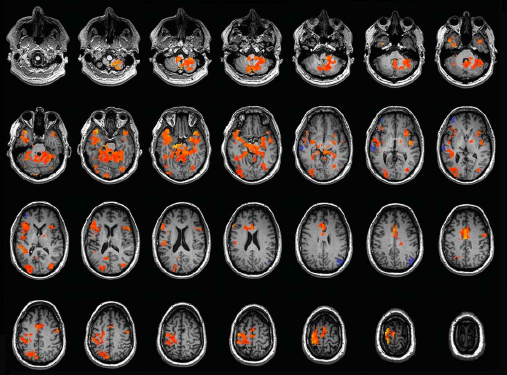

Un cas rarissime de synesthésie émotionnelle après un AVC. À lire sur 'Réalités Biomédicales' https://t.co/EoHnXtdxGo

Un cas unique de synesthésie vient d'être décrit en France : une personne qui associe des couleurs aux sons, à tel point qu'elle doit d'abord "déchiffrer les couleurs" avant de comprendre le sens des mots. #synesthésie

Associer couleur et phonème : focus sur un cas rare de synesthésie, actualité @CNRS. "...la personne aborde le sens des mots de manière atypique (...) via les couleurs associées aux phonèmes. (...) Les mots seuls n’ont pas de sens pour elle." #synesthésie